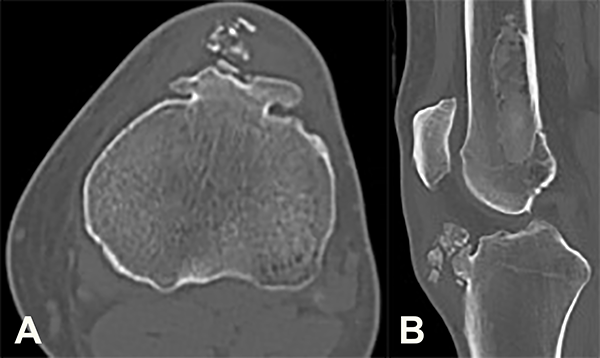

La tomografía computada (TC) reveló una lesión exofítica de contornos irregulares, dependiente de la TAT. Algunas de estas calcificaciones eran subyacentes al TR y otras impresionaban intratendinosas. Además, se observó una imagen endomedular, de contornos netos escleróticos, con patrón de vidrio esmerilado, con contacto con la cortical posterior, sin causar reacción perióstica, ubicada en el sector diafiso-metafisiario distal del fémur (fig. 3).

Figura 3: Corte axial (3a) y sagital (3b) de TAC donde se observa la lesión exofítica de contornos irregulares, dependientes de la TAT. En la metáfisis femoral puede observarse además la lesión esclerosa de bordes bien delimitados (3b).

Se plantean como diagnósticos diferenciales: enfermedad de Trevor, una secuela de Osgood-Schlatter o un osteocondroma. Para establecer este diagnóstico se realizó una biopsia por punción de ambas lesiones guiada por TC (fig. 5).

El resultado de la anatomía patológica informó una proliferación osteocartilaginosa sin atipías la cual, asociada a las características radiológicas, corresponde a una displasia epifisaria hemimélica. En cuanto a la lesión del fémur, los hallazgos histológicos refieren a una displasia fibrosa.

Figura 5: Se observa el sitio de la biopsia guiada bajo TAC en un corte axial de la tibia (5a) y del fémur (5b).